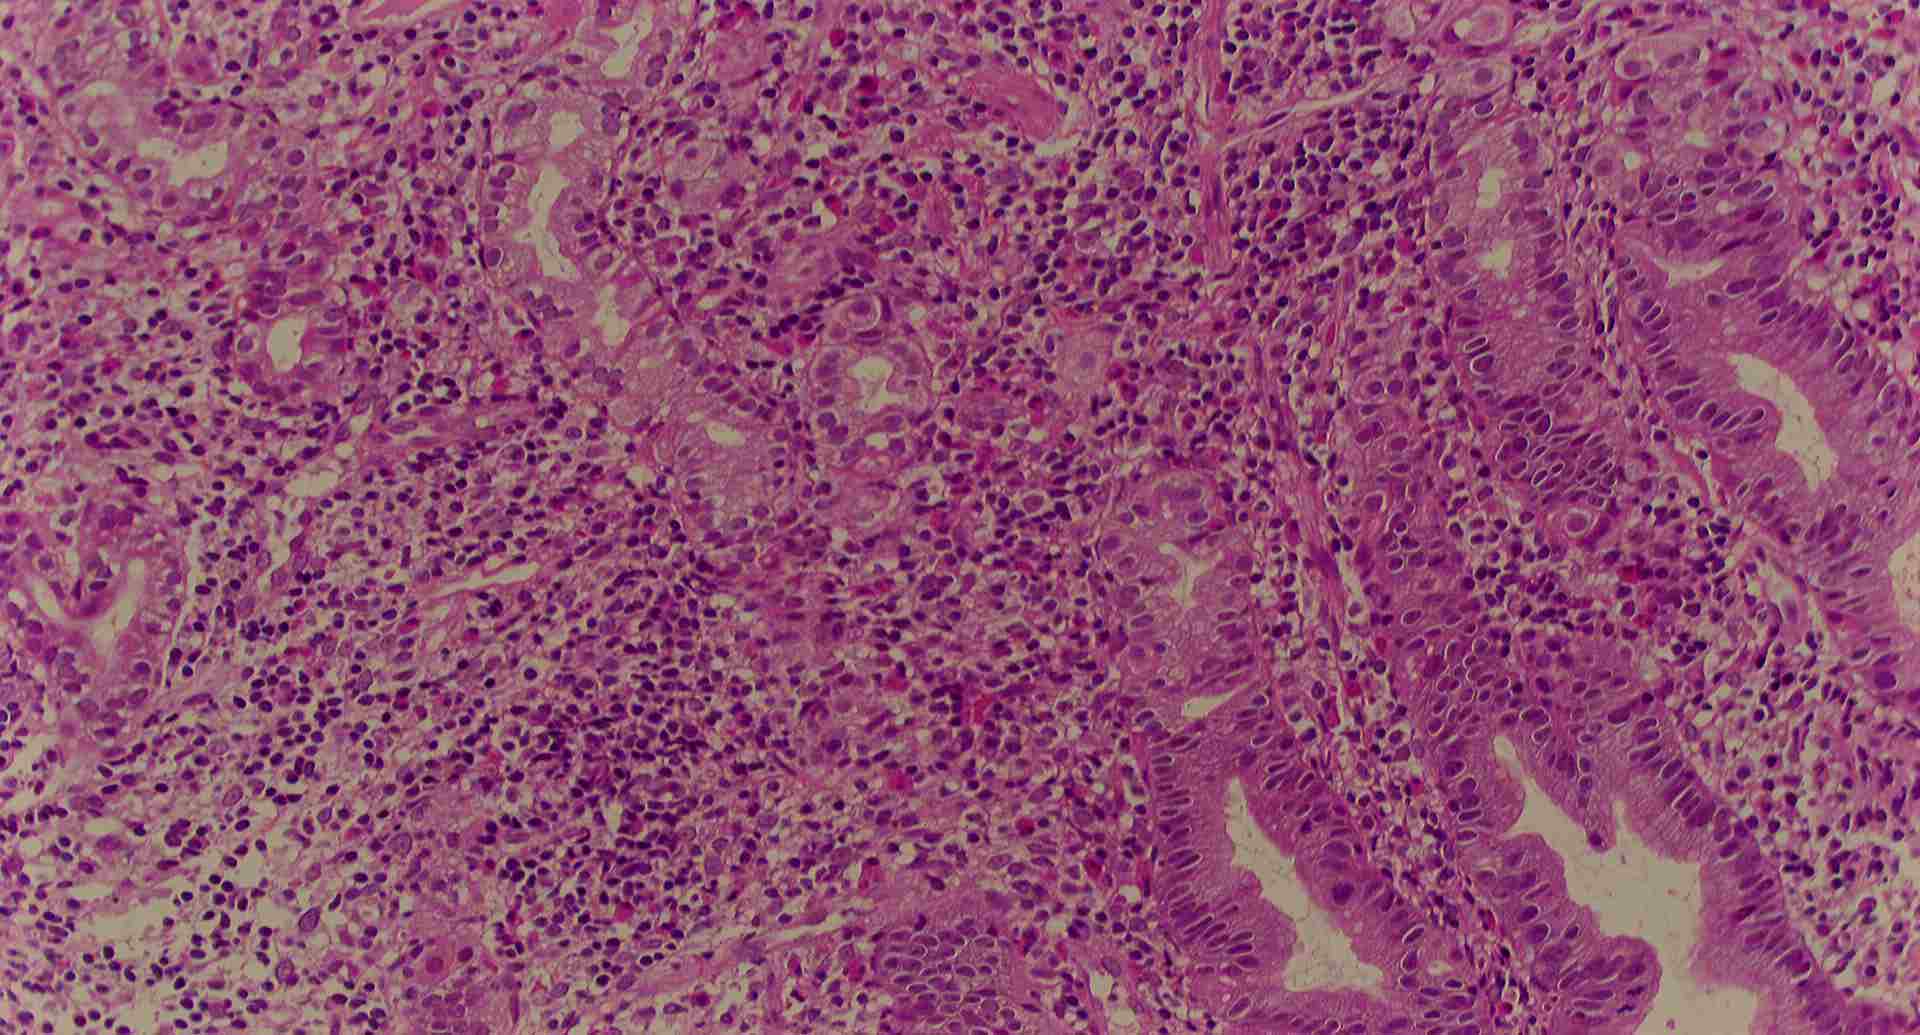

標本13

標本13の説明